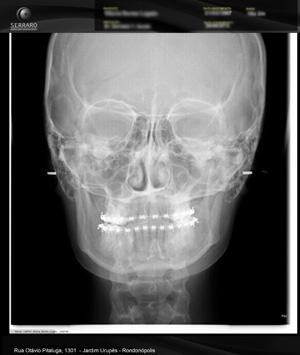

Radiografias do crânio, realizadas a uma distância pré-estabelecida, com o objetivo de diminuir distorções, com o auxílio de um artefato posicionador – cefalostato. Permite mostrar os ossos da face e crânio para avaliação do crescimento, desenvolvimento, relação esqueletal, simetria, estudo de adenóides, processos patológicos e traumáticos. São exames utilizados na prática cirúrgica e ortodôntica, como base para análises cefalométricas, tanto manual como computadorizada.

Utilizada para localização e delimitação de áreas patológicas, de corpos estranhos, determinação das direções, extensões e complexidade das fraturas da mandíbula, vistas principalmente no sentido vestíbulo-lingual.

Possui variações como: PA de Seios da face (Water’s), PA de Mandíbula.